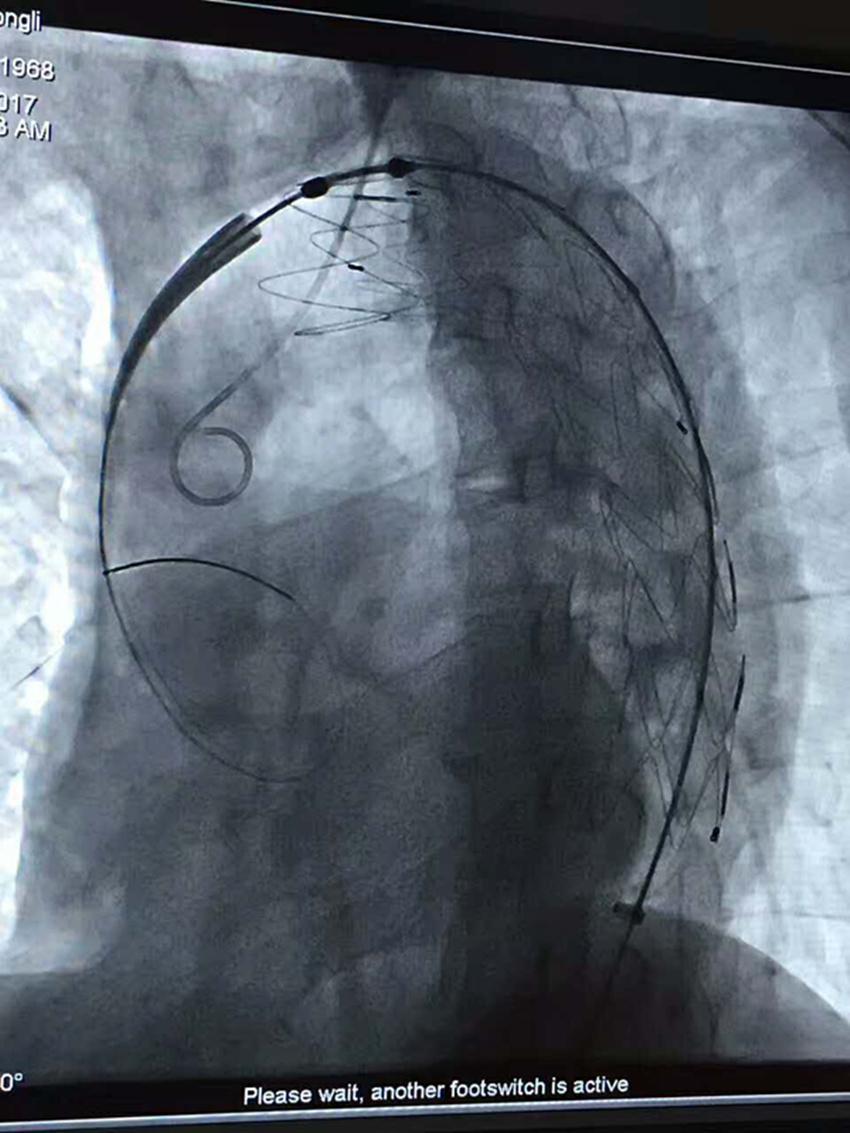

7月15日上午9时,由普外二科汪志刚医师、张文俊主任手术,陆信武教授现场指导,为患者施行局麻,在DSA引导下行经右股动脉穿刺主动脉造影术+主动脉夹层腔内修复术,9:50手术顺利完成。目前病人一切正常,生命体征平稳。

手术进行中